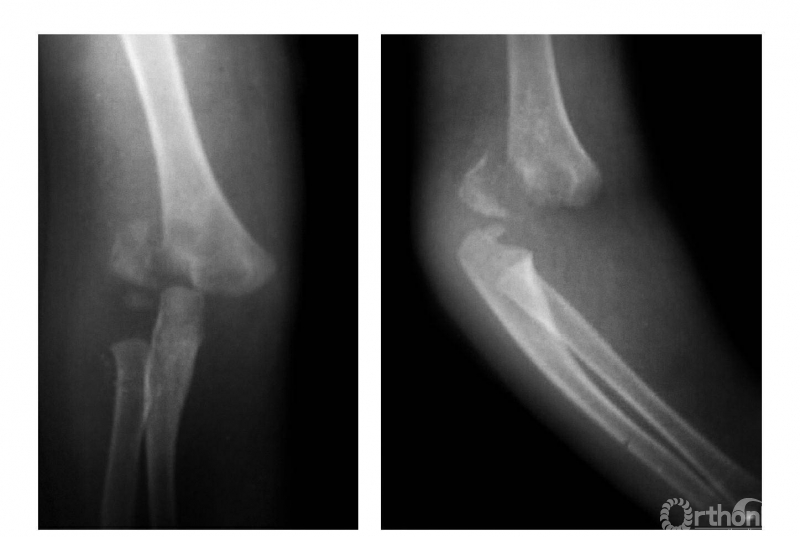

四、屈曲型

例:肱骨下端骨骺分离伴前臂向前移位(图4)。

图4